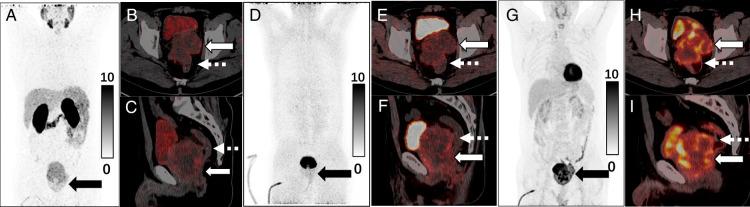

Primary prostate mucinous adenocarcinoma is an exceedingly rare entity with distinct imaging characteristics. We report the case of a 62-year-old man with biopsy-proven prostate mucinous adenocarcinoma. The patient underwent MRI and multi-tracer PET/CT. PET/CT images demonstrated the prostate lesion with moderate uptake of 68 Ga-PSMA and 68 Ga-FAPI, yet significantly high 18 F-FDG uptake. No abnormal radiotracers' uptake was observed elsewhere in the body. Multi-tracer PET/CT findings suggest that 18 F-FDG may be a more suitable radiotracer for the systemic assessment of primary prostate mucinous adenocarcinoma.

原发性前列腺黏液腺癌是一种极为罕见的疾病,具有独特的影像学特征。我们报告一例经活检证实为前列腺黏液腺癌的62岁男性病例。该患者接受了MRI和多示踪剂PET/CT检查。PET/CT图像显示前列腺病变对68Ga-PSMA和68Ga-FAPI有中度摄取,但18F-FDG摄取显著增高。身体其他部位未观察到放射性示踪剂的异常摄取。多示踪剂PET/CT检查结果表明,18F-FDG可能是对原发性前列腺黏液腺癌进行全身评估更合适的放射性示踪剂。